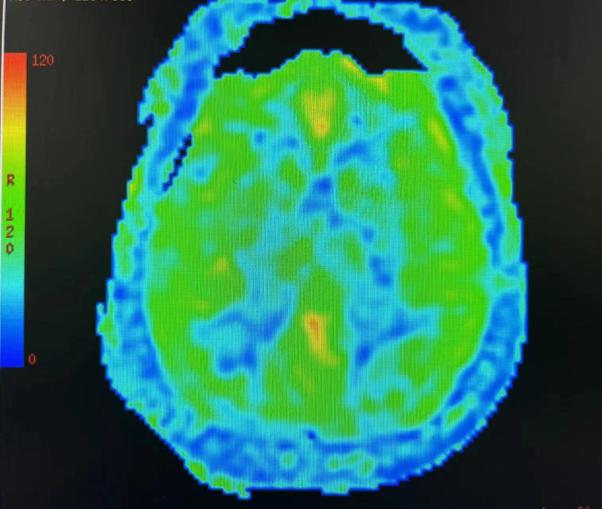

磁共振脑灌注成像提示,老李双侧大脑半球的脑血流对称性减少,说明重度狭窄已导致了相应区域的供血不足。

磁共振灌注成像提示双侧大脑半球脑血流对称性较少